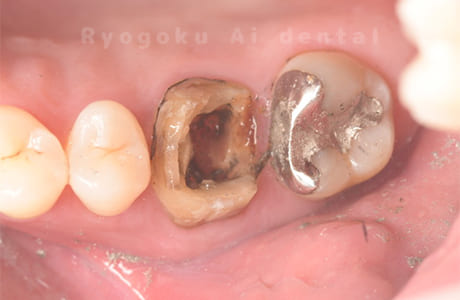

- 原因

- 重度カリエス

-

- 治療内容

- 抜髄治療、マイクロエンド

- 治療費用

- 99,000円

- 担当医

- Dr. 炭野

虫歯が大きく、神経の保存ができなかったため、マイクロエンド治療を行いました。